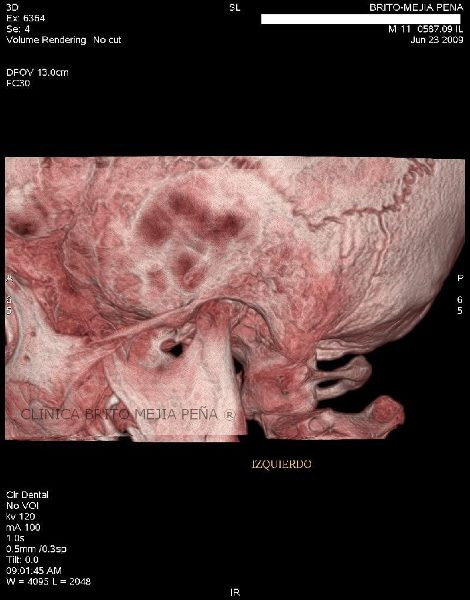

Cabeza y Cuello 2

Envíado por BMP Imágenes Diagnósticas

BMP Imágenes Diagnósticas